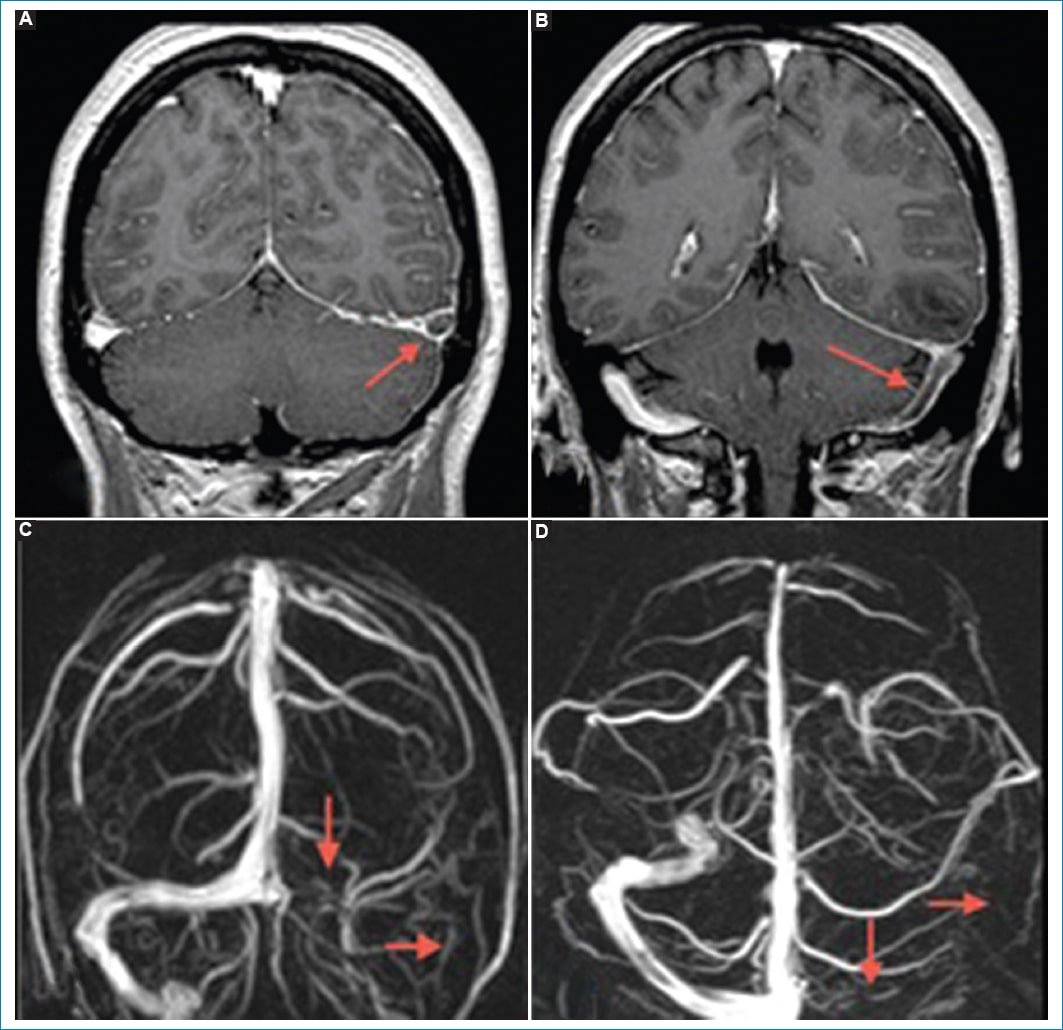

Figura 4. Trombosis venosa cerebral. Cortes coronales de RM en secuencia T1 con gadolinio A y B: Se identifica un defecto de relleno a nivel del seno venoso transverso del lado izquierdo que se extiende al seno sigmoideo homolateral (flechas). Dichos hallazgos se correlacionan con ausencia de señal de la estructura mencionada en la reconstrucción 3D de la angio-RM venosa (C y D).